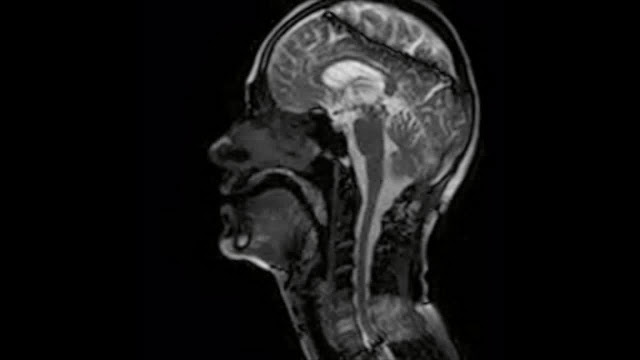

Immagine: Freitas A, Wylezinska M, Birch M, Petersen S, Miquel M, CC BY 4.0 <https://creativecommons.org/licenses/by/4.0>, via Wikimedia Commons

Una nuova ricerca indica che l’effetto placebo funziona e la suggestione non c’entra. Il placebo attiva specifiche aree del tronco encefalico coinvolte nella percezione del dolore. Lo studio che le ha identificate potrebbe aprire la strada allo sviluppo di terapie del dolore che potenziano l’effetto placebo. Ora si sa dove indirizzarle.

La percezione del dolore può essere fortemente influenzata dalle aspettative e dalle convinzioni di un individuo. Mentre il circuito corticale responsabile della modulazione del dolore è stato studiato a fondo, le vie del tronco cerebrale coinvolte nei fenomeni modulatori dell'analgesia placebo e dell'iperalgesia nocebo restano da affrontare direttamente. Questo studio ha impiegato la risonanza magnetica funzionale 7 Tesla (fMRI) ad altissimo campo per determinare con precisione le differenze nei circuiti del tronco cerebrale presenti durante la generazione di analgesia placebo e iperalgesia nocebo in partecipanti umani sani (N = 25; 12 maschi). Per due giorni consecutivi, attraverso l'applicazione cieca di stimoli termici alterati, i partecipanti sono stati ingannevolmente condizionati a credere che due creme inerti etichettate "lidocaina" (placebo) e "capsaicina" (nocebo) agissero per modulare il loro dolore rispetto a una terza "vaselina" (controllo) crema. In una successiva fase di test, sono stati raccolti set di immagini fMRI mentre ai partecipanti sono stati dati stimoli nocivi identici a tutti e tre i siti di crema. Sono state raccolte le valutazioni dell'intensità del dolore e sono state determinate le risposte al placebo e al nocebo. L'analisi fMRI specifica del tronco cerebrale ha rivelato un'attività alterata nei principali nuclei modulatori del dolore, incluso un reclutamento disparato del percorso grigio periacqueduttale (PAG) - midollo ventromediale rostrale (RVM) quando sono stati osservati sia maggiori effetti placebo che nocebo. Inoltre, abbiamo scoperto che le risposte placebo e nocebo attivavano in modo differenziale il nucleo parabrachiale ma si sovrapponevano nel loro impegno della substantia nigra e del locus coeruleus. Questi dati rivelano che gli effetti placebo e nocebo sono generati attraverso l'impegno differenziale del percorso PAG-RVM, che di concerto con altri siti del tronco cerebrale probabilmente influenza l'esperienza del dolore modulando l'attività a livello del corno dorsale.

La comprensione dei meccanismi di modulazione del dolore endogeno sosterrebbe lo sviluppo di strategie di trattamento clinico efficaci per il dolore sia acuto che cronico. È noto da tempo che specifici nuclei del tronco cerebrale svolgono un ruolo centrale nella modulazione nocicettiva, tuttavia a causa delle loro piccole dimensioni e organizzazione complessa, i precedenti sforzi di neuroimaging sono stati limitati nell'identificare direttamente come queste reti subcorticali interagiscono durante lo sviluppo di effetti anti- e pro-nocicettivi. Abbiamo utilizzato la risonanza magnetica ad altissimo campo per determinare le strutture del tronco cerebrale e misurare il cambiamento del segnale durante l'analgesia placebo e l'iperalgesia nocebo. Riteniamo i circuiti del tronco cerebrale sovrapposti e disparati responsabili dell'alterazione della percezione del dolore. Questi risultati estendono la nostra comprensione dell'organizzazione dettagliata e della funzione dei nuclei discreti del tronco cerebrale coinvolti nell'elaborazione e nella modulazione del dolore."